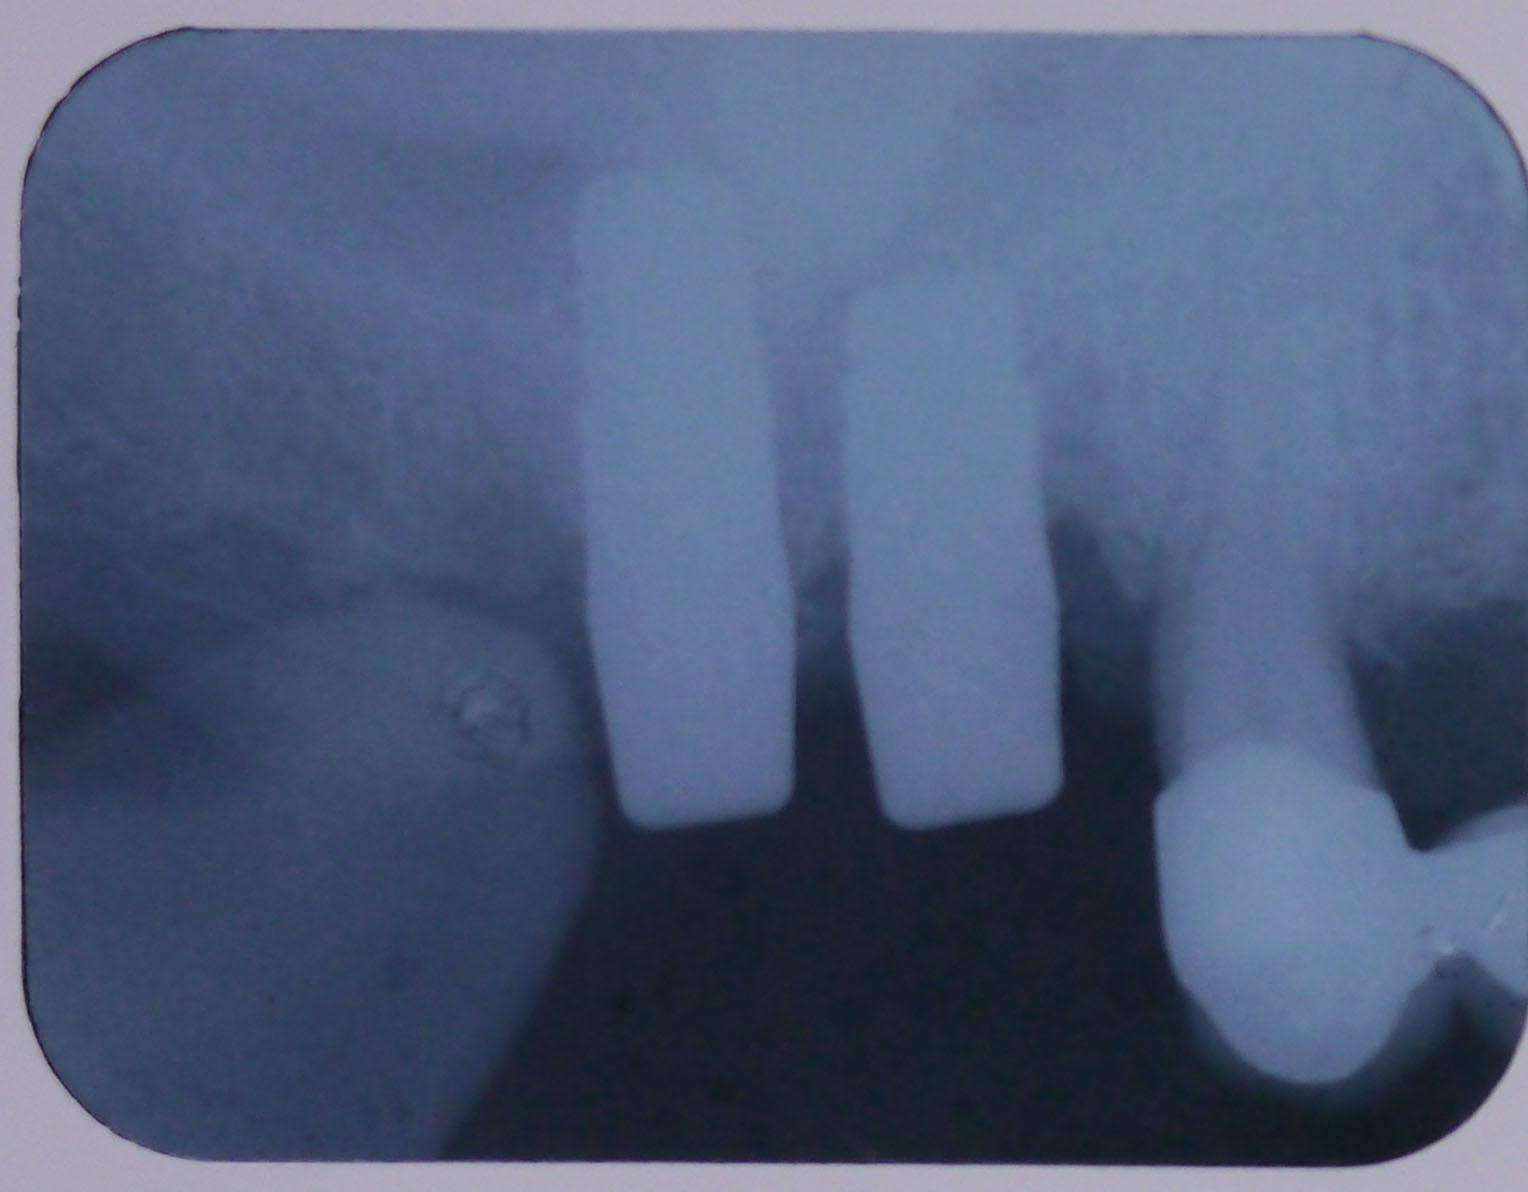

レントゲン画像1

平成24年9月11日の手術後のレントゲン画像

レントゲン画像2

平成25年1月16日、4ヶ月後のレントゲン画像